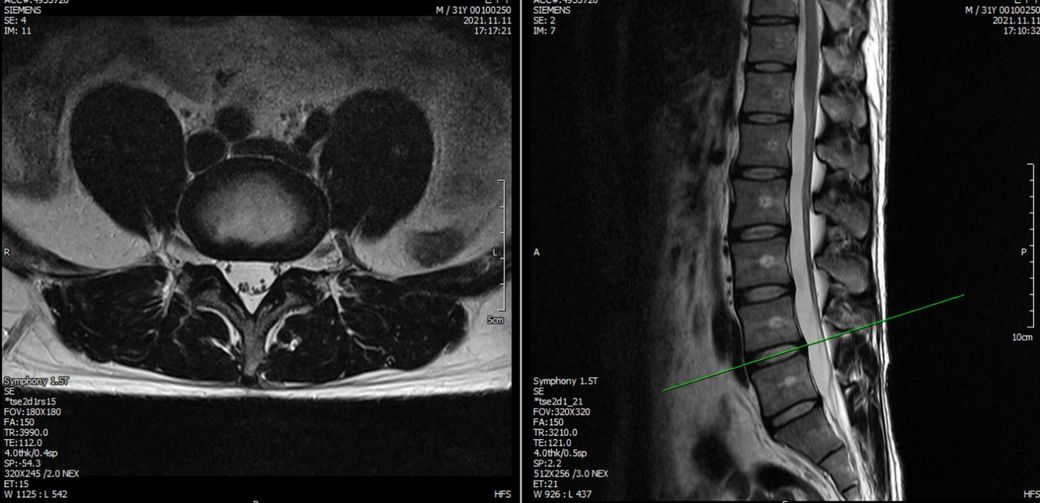

21년도와 24년도 각각 찍은 L spine 사진입니다.

2021년 영상